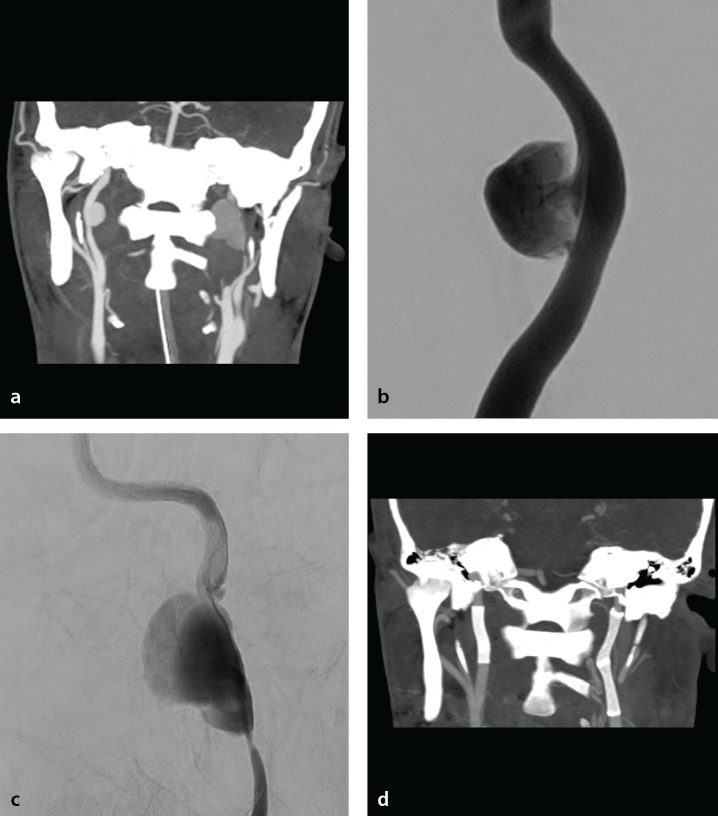

Abstract Image